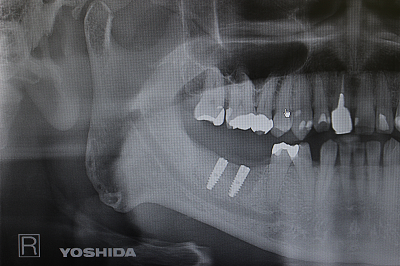

【インプラント】精密検査と多様な術式への対応

アンキロスインプラント(純チタンインプラント)

インプラント治療は、失った歯の機能を回復させる有効な選択肢の一つですが、顎の骨の状態や全身の健康状態によって適した方法は異なります。安全性と長期的な安定性を確保するためには、十分な術前検査と的確な診断が重要です。吉井歯科クリニックでは、被ばく線量を抑えつつ高画質の画像が得られるCTを用いて、骨の質や厚み、神経の位置まで詳細に確認し、患者様に分かりやすくご説明したうえで治療計画を立てています。

使用するインプラントには、純チタン製で表面処理が施されたアンキロスインプラントや、骨との結合を高めるHAコーティングのスプラインインプラントなど、特性の異なる種類があります。また、骨の厚みが不足している場合には、専用の器具を用いた術式や骨の厚みを補う処置にも対応しています。吉井歯科クリニックは、精密な分析に基づいて埋入方向や深度を決定し、患者様一人ひとりに適したインプラント治療を提供しています。